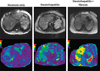

Magnetic resonance elastography (MRE) has been successfully implemented in the assessment of diffuse liver diseases. Currently, MRE is the most accurate noninvasive technique for detection and staging of liver fibrosis with a potential to replace liver biopsy. Magnetic resonance elastography is able to differentiate isolated fatty liver disease from steatohepatitis with or without fibrosis. Potential clinical applications include the differentiation of benign and malignant focal liver masses and the assessment of treatment response in diffuse liver diseases.